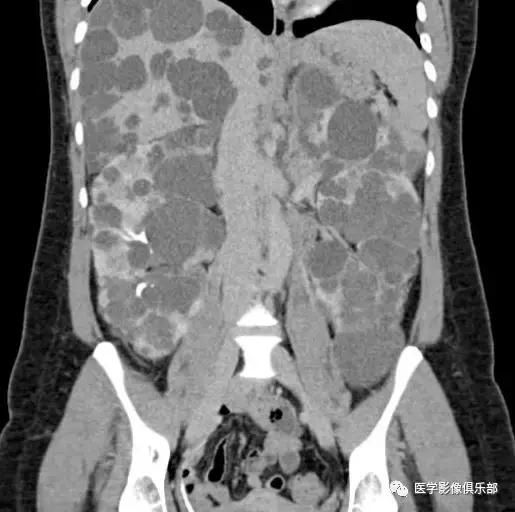

[典型病例二]:45岁,女性患者,腹部不适。家族史是动脉瘤性蛛网膜下腔出血和肾损害。

CTMPR冠状位重建显示双侧肾脏体积明显增大,肾脏皮质及髓质分界不清,弥漫大小不等的囊肿,边界光滑锐利,肝脏实质内亦可见多发大小不等的囊肿。